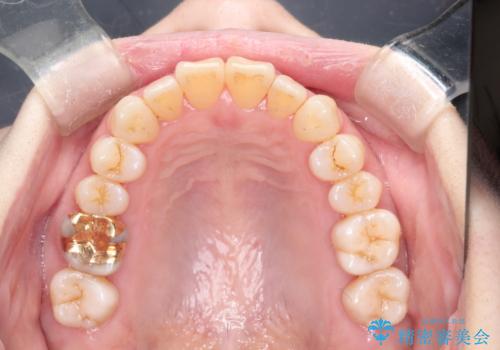

インビザラインによる矯正治療(非抜歯) 上下前歯の開き(開咬)と上下のガタつき(叢生)の改善

- 上下の前歯の開き(開咬)と上下前歯にガタつき(叢生)が見られます。

マウスピース矯正ではメカニクス的に開咬へのアプローチが容易です。

インビザラインの特色を生かした歯牙移動計画を作成し、非抜歯にて治療を行いました。